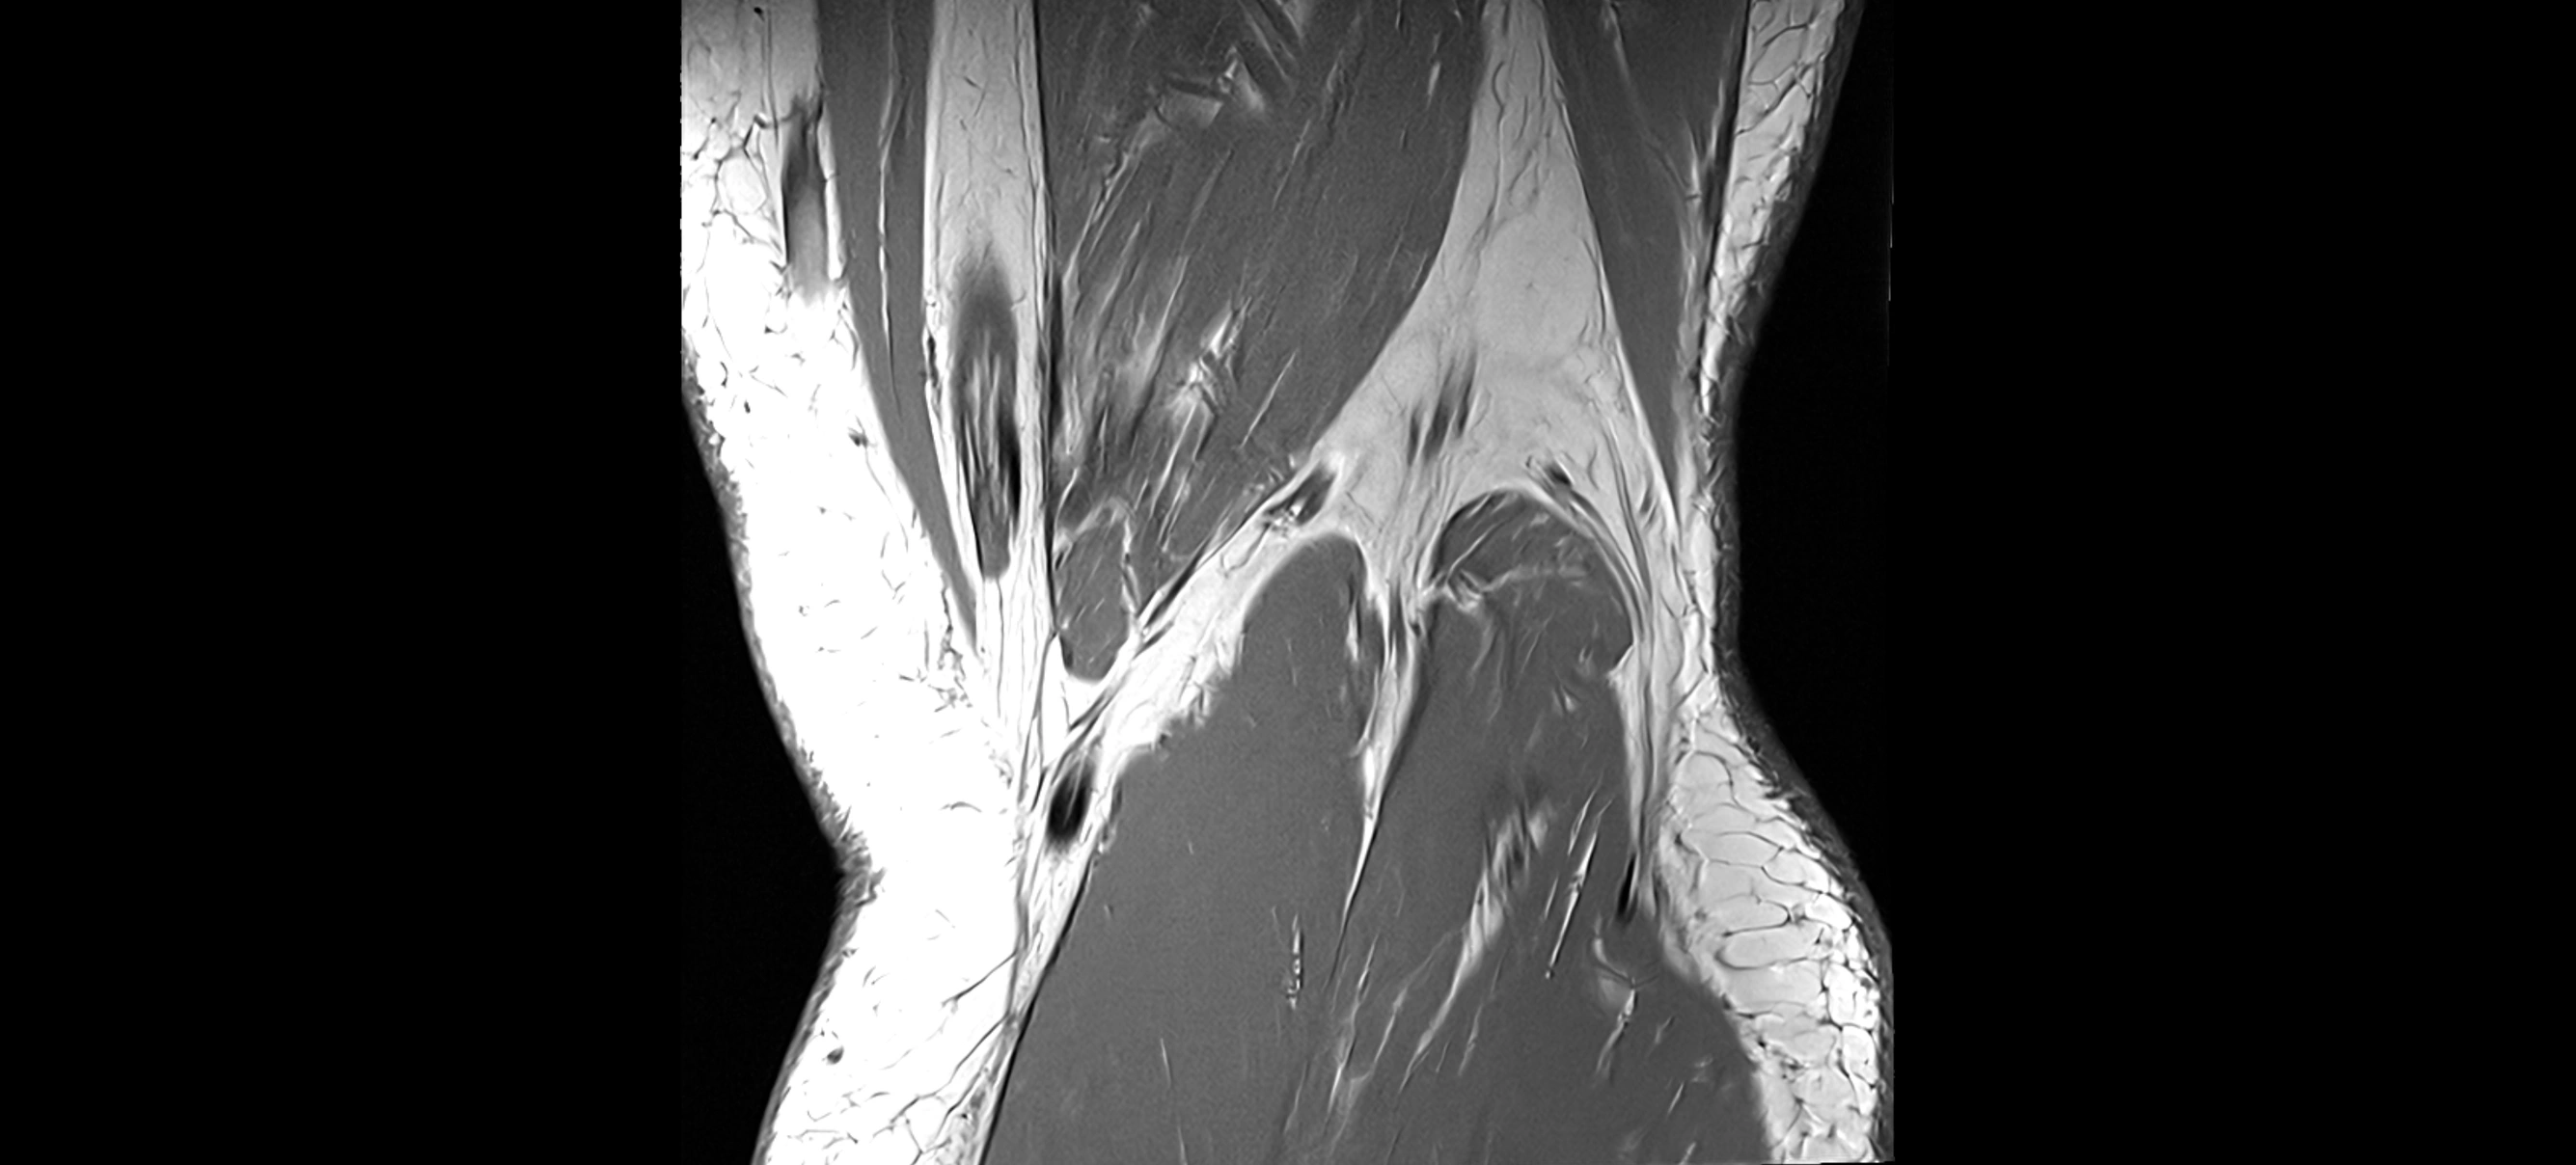

MRI images

image

MRI Appearance

T1-weighted images:

• Normal ACL appears as a low-signal band-like structure crossing the intercondylar notch

• Surrounded by intermediate signal synovial fluid and fat planes

T2-weighted images:

• Normal ACL remains low signal

• Partial or complete tears appear as discontinuity, increased signal, or fiber laxity

STIR (Short Tau Inversion Recovery):

• Normal ACL shows dark low signal

• Acute injury shows bright hyperintensity due to edema and hemorrhage

Proton Density Fat-Saturated (PD FS):

• Normal ACL: dark, low-signal band

• Tears: bright intraligamentous hyperintensity, discontinuity, or abnormal course